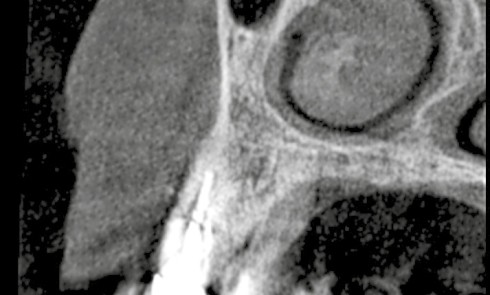

Article réservé à nos abonnés À propos d’une sinusite maxillaire chronique

Questions 1. Quelle est l’étiologie de la sinusite maxillaire gauche ? a. Dépassement de pâte dentaire b. Comblement osseux préimplantaire...